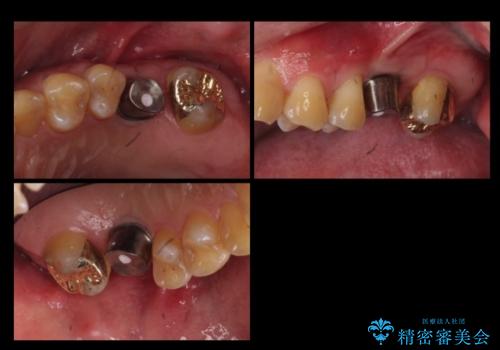

左上6:インプラント(ストローマン)20万円、カスタムアバットメント10万円、スクリューリテイン仮歯2万円、ジルコニアクラウン10万円、ソケットリフト10万円、マイナーGBR 5万円、静脈麻酔(麻酔認定医)5万円

左上7・左下7:PGAインレー 各6万円

左下5:仮歯 1万円、ジルコニアクラウン10万円、ファイバーコア 2万円

左下6:仮歯1万円、ジルコニアクラウン10万円

クラウンは全てスタンダードです。